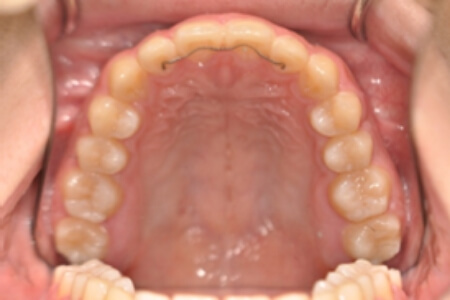

動的治療終了時

症例 症例 症例 症例 症例

治療としては、非抜歯の上、マウスピース矯正装置(インビザライン)で配列を行いました。顎間ゴムの協力もあり、咬み合わせがきれいに改善されました。